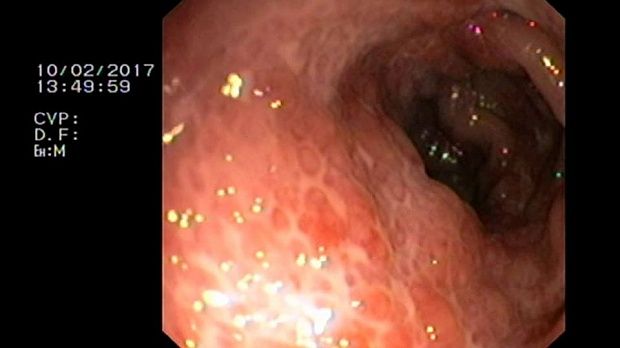

2 мл ( это мин сум, а мы делаем до 10 мл 3% перекись+200 мл физ раствора